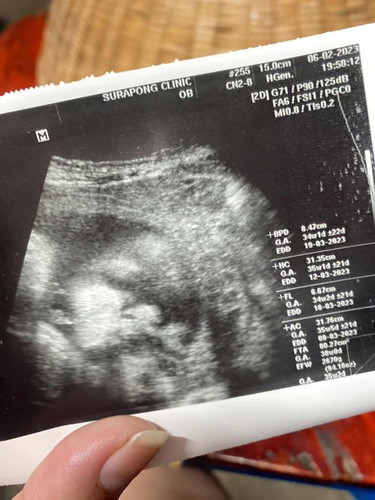

ตั้งท้องได้ 35 week ค่ะ นน. น้อง 2,670 กรัม ค่ะ ช่วงนี้ น้องดิ้นน้อยลง ไม่ดิ้นแรง เหมือนแต่ก่อน ถือว่าปกติ มั๊ยค่ะ หรือน้องตัวใหญ่ไป แม่แอบกังวลค่ะ รบกวนขอคำแนะนำแม่ๆ หน่อย จ้า 🙏🏻♥️

น้องหน้าจะตัวใหญ่ ถ้าน้องดิ้นถึง10ครั้งก็ปกติค่ะแม่ แต่วันนึงไม่ถึง10ครั้ง ให้ไปหาหมอได้เลยค่ะ🥰 น้องจ้ำมั้มมากค่ะ ดูแก้มน้องสิ่ หน้าหยิกมากกก😂❤️